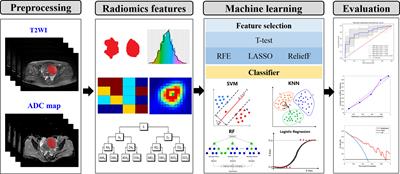

ORIGINAL RESEARCH

Published on 10 Sep 2021